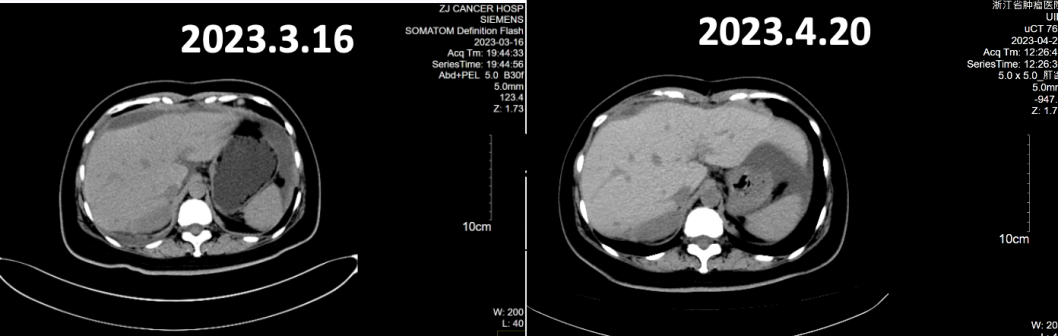

全腹CT(2023年3月16日):盆腔见囊实性灶,肝表面、大网膜及盆底腹膜多发结节灶,考虑转移,较前似饱满。腹盆腔积液,较前增多。右侧斜裂胸膜不均匀增厚,较前明显,转移考虑。右侧胸腔积液,较前增多。右侧心膈角增大淋巴结,较前缩小,考虑转移。疗效评价为疾病进展(PD)。

全腹CT:肝表面、腹膜、肠表面及盆腔系膜多发结节灶及增厚,考虑转移,部分较前稍缩小;腹盆腔积液,较前稍吸收。右侧斜裂胸膜不均匀增厚,较前缩小,转移考虑。右侧胸腔少量积液,较前明显吸收。双侧心膈角增大淋巴结,较前缩小,考虑转移。疗效评价为部分缓解(PR)。